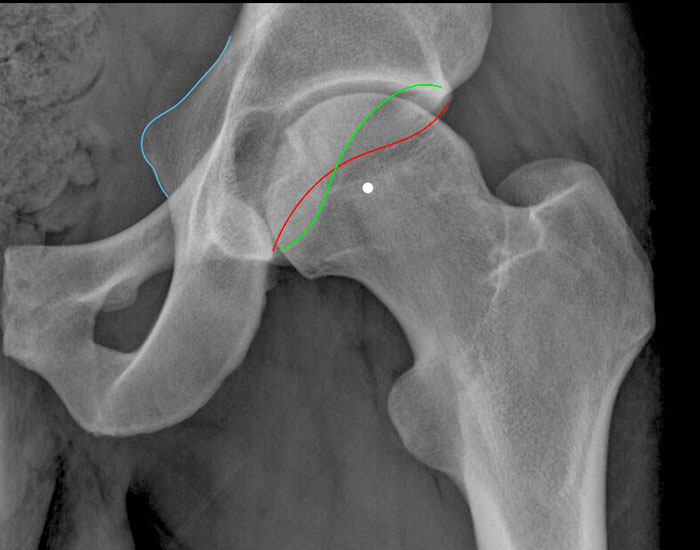

Góc nghiêng trước bình thường của ổ cối

Đây là hình ảnh chi tiết của khớp háng trái bình thường trên phim X-quang khung chậu tư thế thẳng.

Các số đo này luôn phải được đánh giá trên phim X-quang khung chậu chứ không phải phim chụp tập trung vào một khớp háng đơn lẻ.

Do hướng nghiêng trước bình thường của ổ cối, bờ thành trước (đường đỏ) chiếu về phía trong so với thành sau (đường xanh lá), tức là không có hiện tượng giao thoa.

Thành sau nhô ra ngoài đến trung tâm của chỏm xương đùi, tức là không có dấu hiệu thành sau.

Gai ngồi (đường màu xanh) không nhô ra phía trong, tức là không có dấu hiệu gai ngồi.

Nghịch chiều ổ cối

Trên phim X-quang, các dấu hiệu của nghịch chiều ổ cối bao gồm:

Dấu hiệu giao chéo – thành trước (đặc biệt là phần trên) chiếu ra ngoài so với thành sau.

Dấu hiệu thành sau – thành sau chiếu vào trong so với tâm của chỏm xương đùi.

Dấu hiệu gai ngồi – gai ngồi chiếu vào trong nhiều hơn bình thường.

Nếu chỉ có dấu hiệu giao chéo dương tính, được gọi là kẹp cục bộ (anterosuperior).

Khi

cả dấu hiệu thành sau và dấu hiệu gai ngồi cũng dương tính,

được phân loại là kẹp toàn bộ/lật ngược ổ cối.

Đây là chi tiết của một X-quang Khung chậu tư thế thẳng (AP).

Trước tiên hãy quan sát kỹ hình ảnh.

Then scroll to the next image.

Findings

- Dấu hiệu giao chéo – phần trên của thành trước ổ cối (đường đỏ) kéo dài ra ngoài vượt qua thành sau ổ cối.

- Dấu hiệu thành sau – thành sau nhô ra phía trong so với trung tâm của chỏm xương đùi.

- Dấu hiệu gai ngồi – gai ngồi nhô vào trong nhiều hơn bình thường (đường màu xanh).

Những

phát hiện này phù hợp với hình thái kẹp toàn bộ do nghịch chuyển ổ cối.

Notice that there is also some cam-morphology.